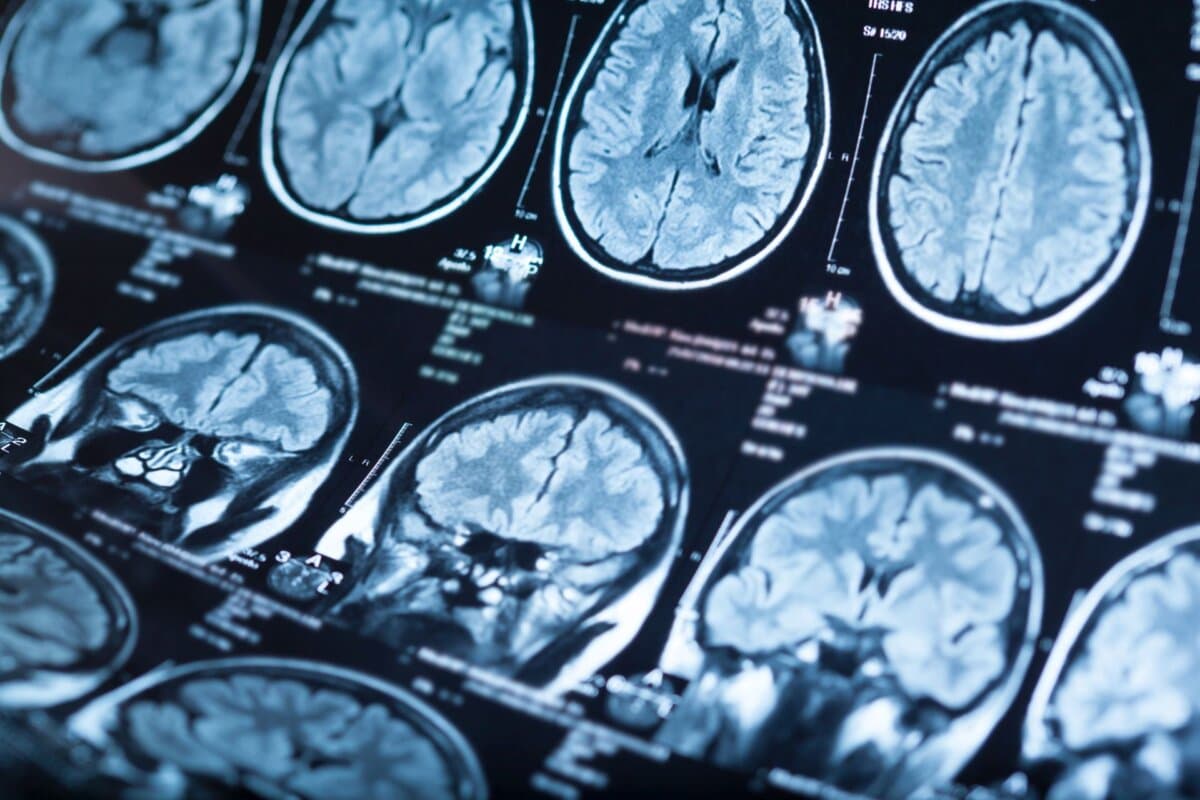

Bisher wird die MS bei typischen Zeichen eines klinisch isolierten Syndroms mit der Detektion oligoklonaler Banden gesichert. Der Nachteil: Man benötigt eine Liquorpunktion. Eine schonende Alternative könnte das zentrale Venenzeichen bieten, bei dem lediglich ein MRT mit T2-gewichteter Sequenz erforderlich ist.